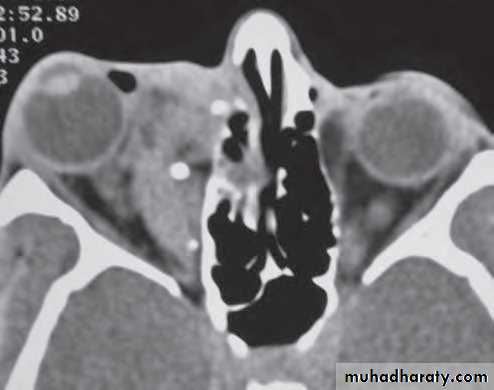

CT shows the bony defect responsible for the herniation.

Imaging (e.g. MRI and magnetic resonance venography (MRV), CT, ultrasound venography) shows a lobulated mass with variable contrast enhancement, and may demonstrate phleboliths.